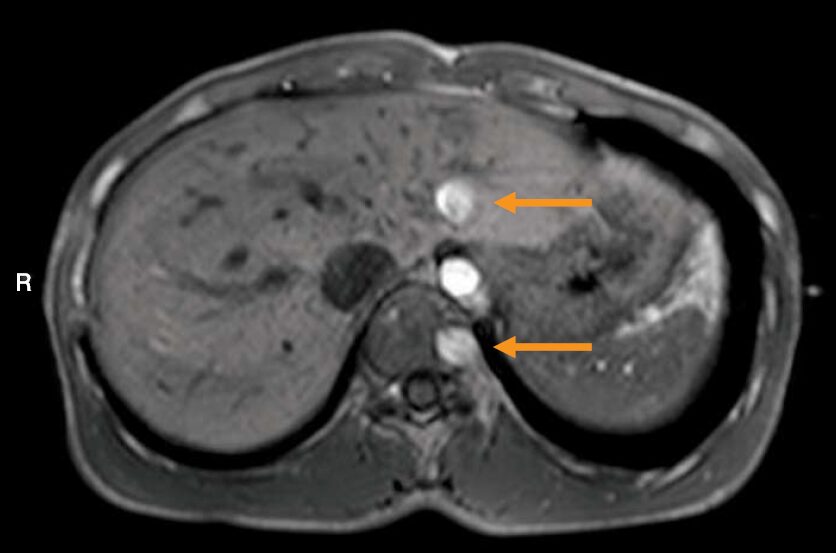

MR像示す。印で示すアーチファクトの原因はどれか。

この画像に写っている矢印のアーチファクトは、モーションアーチファクトの一種で、特に動脈の拍動のような周期的な動きによって生じる「ゴーストアーチファクト」です。

MRIでも同じことが起こります。 動脈の拍動は、この「点滅するネオンサイン」と同じです。ゆっくりとした位相エンコードの間に、ドクンドクンと周期的に動くため、その信号が本来の位置からズレた場所に複数記録されてしまい、位相エンコード方向に沿って淡いゴーストとして現れるのです。

- 大位相エンコード方向に沿って、同じ構造が周期的に繰り返し写るゴースト像として現れます。

学生がよく間違えるのは、「黒い影=磁化率」「位置のズレ=化学シフト」と、キーワードだけで早とちりすることじゃ。しかし、この画像で最も特徴的なのは、同じ構造(大動脈)が等間隔に並んで見えている点。これに気づけば、「周期的な動きによるゴーストだ」と判断できるはず。

- 腹部MRIでは、大動脈のゴーストが肝臓や膵臓に重なり、腫瘍やリンパ節と紛らわしく見えることがあります。これをアーチファクトだと見抜けなければ、誤診に繋がる危険があります。